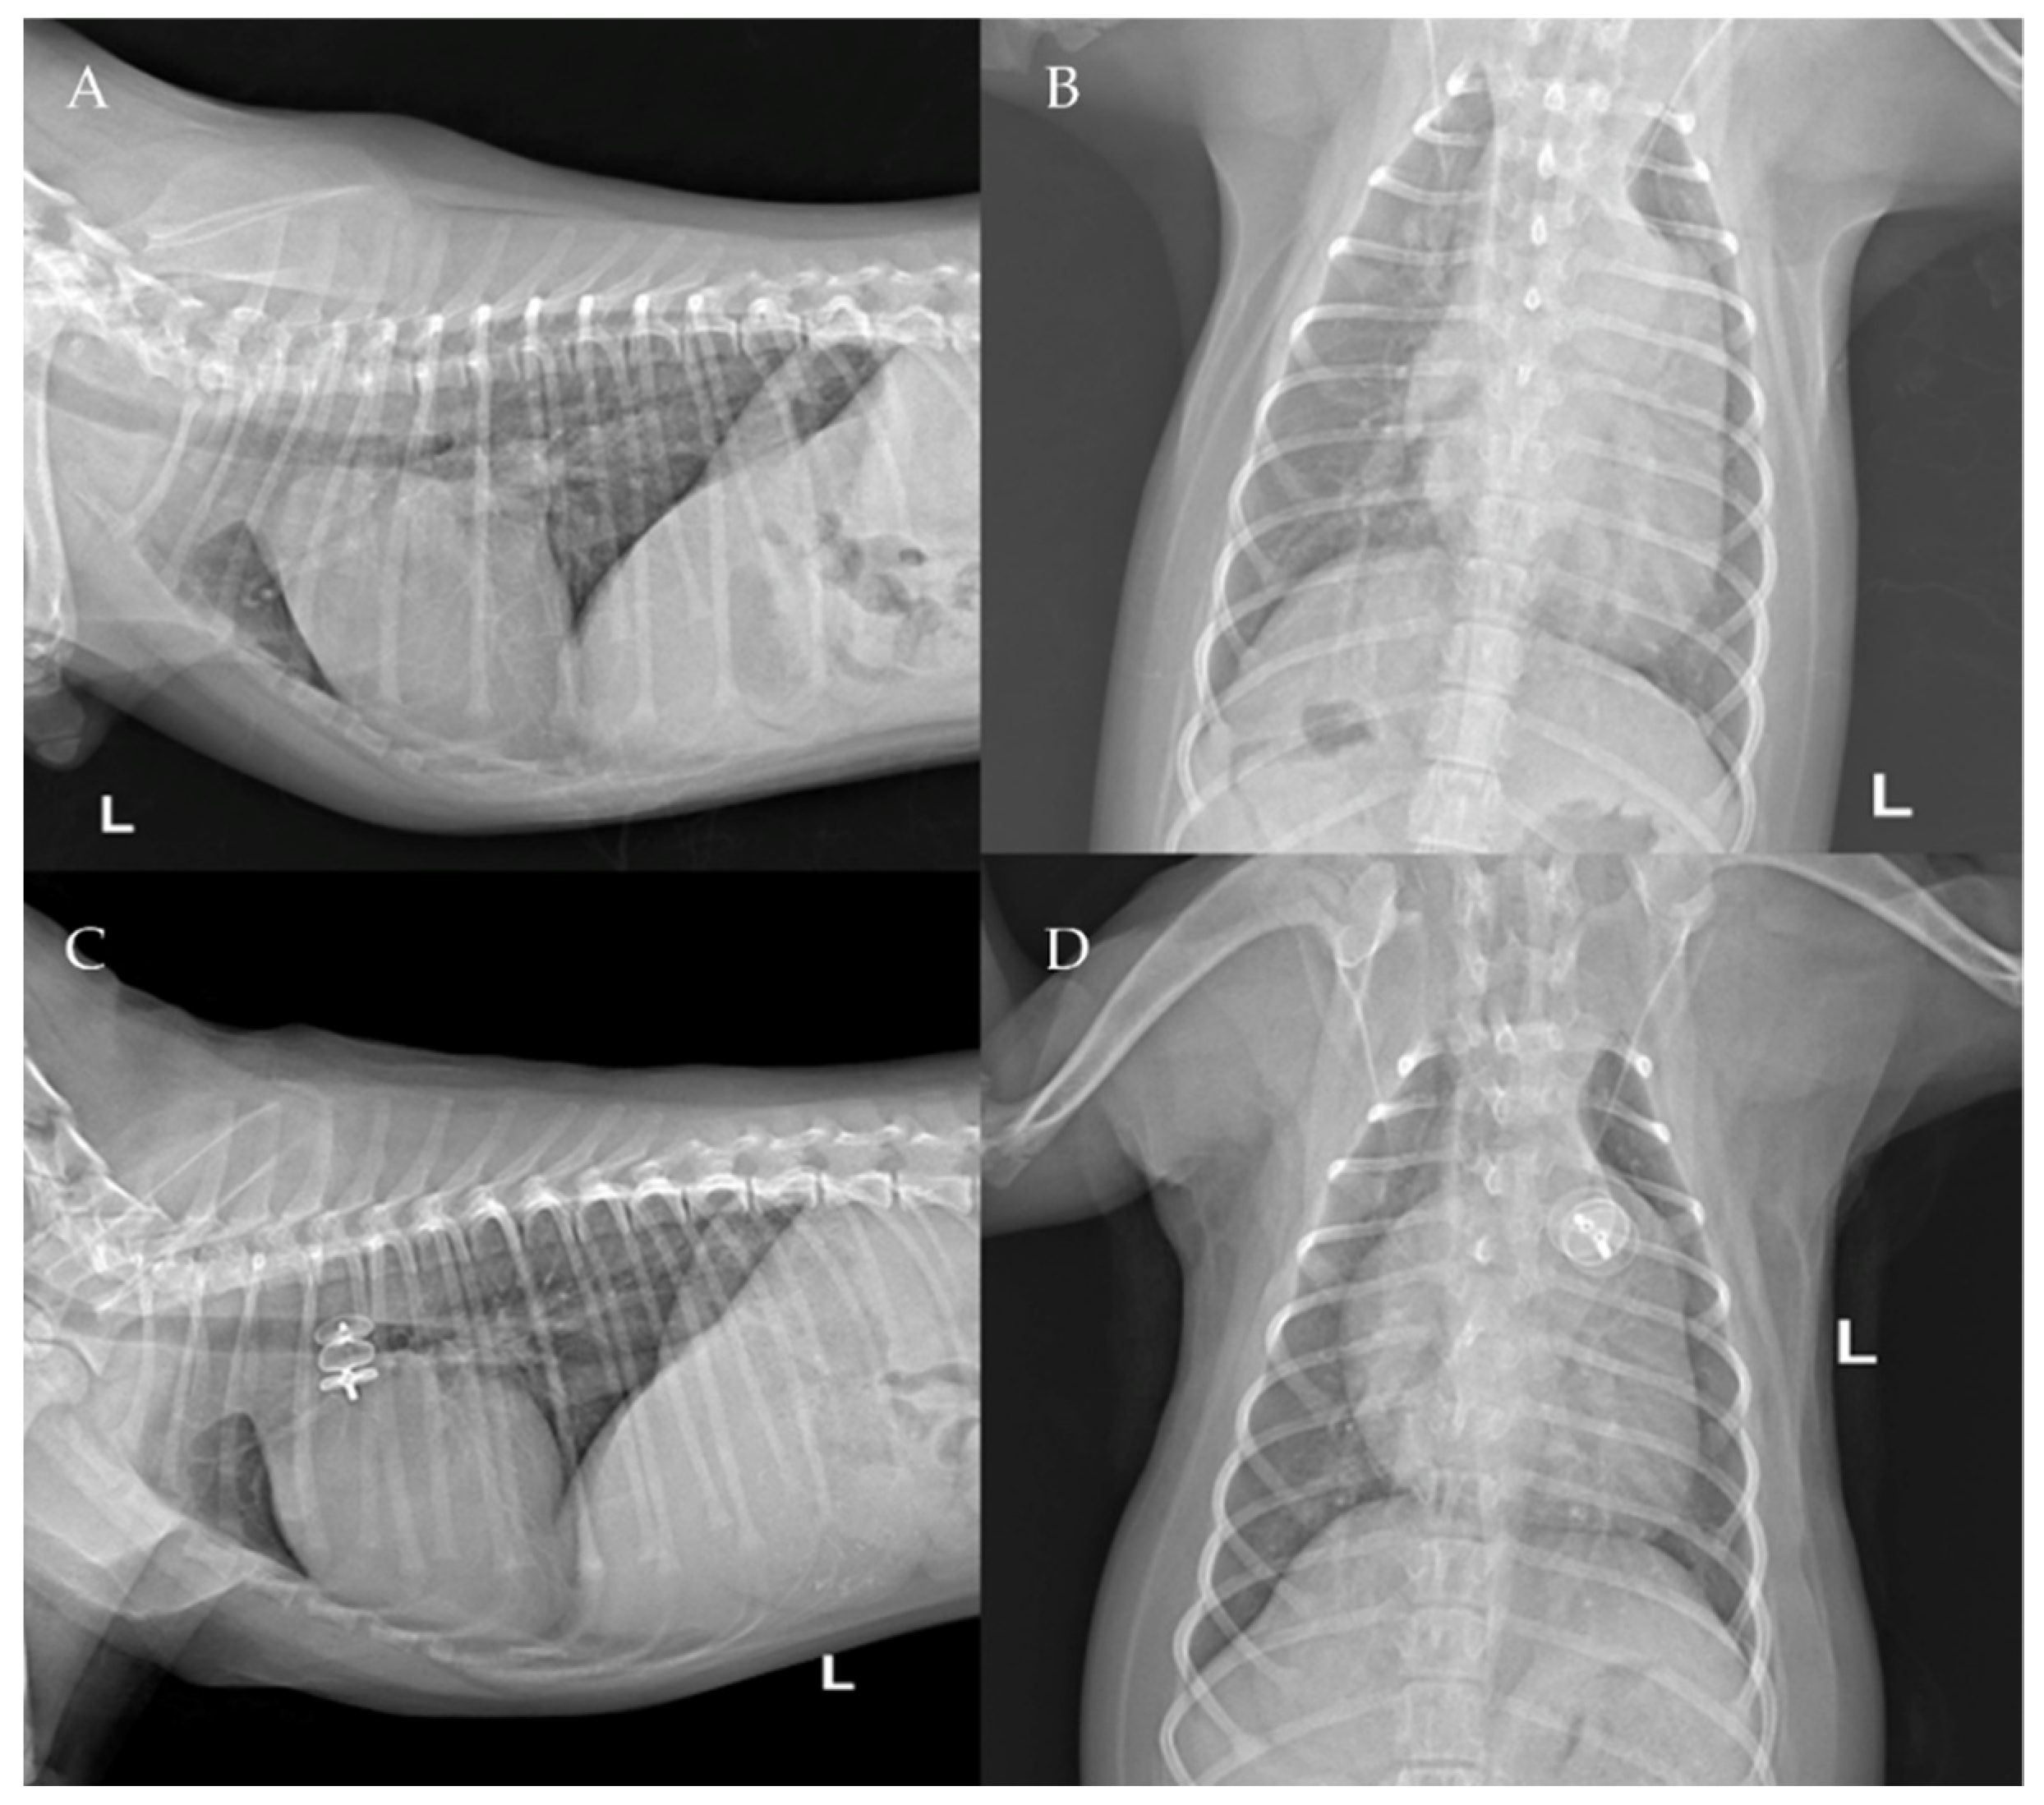

Figure 11. Pre-procedure (A,B) and post-procedure (C,D) right lateral and dorso-ventral thoracic radiographs of Case 6.

The thoracic radiographs performed before and just after the procedure showed a reduction in the cardiac silhouette as well as significant reduction of the over-circulation vascular pattern for all dogs (Figure 8, Figure 9, Figure 10, Figure 11 and Figure 12).